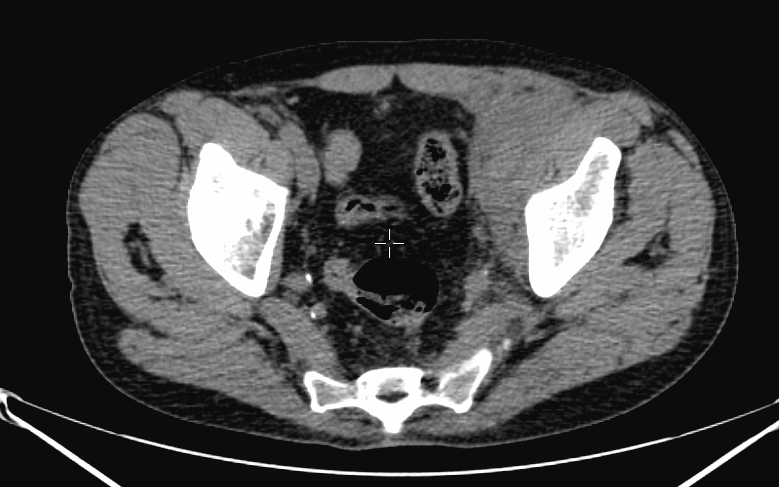

The most common indication of bone scintigraphy is the evaluation of bone metastasis. (Figure 5.)

Image

a

b

c

d

5. Multiplex bone metastases. Bone scintigraphy, anterior (a) and posterior (b) whole body scans. SPECT-CT sagittal plane, fusion image (c) and CT image (d). Obvious bone structural changes cannot be identified on the CT scan yet.

The examination is appropriate for staging a malignant process and following-up bone metastases. It is clinically most suitable for lesions that frequently present bone metastasis, primarily in case of prostate-, breast-, lung cancer and neuroblastoma. It is, however only indicated in cases where the soft tissue involvement of the tumor is big enough to suggest a higher incidence of bone metastasis; before radical surgeries and for the selection of patients who would benefit form a palliative radionuclide therapy. Otherwise, scintigraphy is advisable in case of any primary tumor, if the suspicion for metastasis is raised, e.g.: bone pain, pathologic radiological or lab results (elevated serum ALP and tumor marker levels). Bone metastases in most cases are located in bones that contain red bone marrow (skull, vertebrae, ribs, sternum, pelvic bones and the proximal bone segments of the limb) and usually show a multiplex appearance. Activity increase can be seen typically, metastases that cause activity decrease are rare; they could occur in cases of thyroid gland tumor, renal carcinoma, lymphoma and multiple myeloma. Solitary lesions or a few lesions only, due to the aspecific nature of the examination, cause a differential diagnostic problem in many cases, for example vertebral degenerative processes can mimic metastatic activity. Equivocal lesions usually require further, targeted radiological investigations. A negative X-ray examination does not rule out the possibility of a metastatic lesion, since the isotope scan is more sensitive. Therefore, it is possible that it could already be detecting an existing metastasis, while X-ray is still insensitive and unable to show the lesion. (Figure 5.)